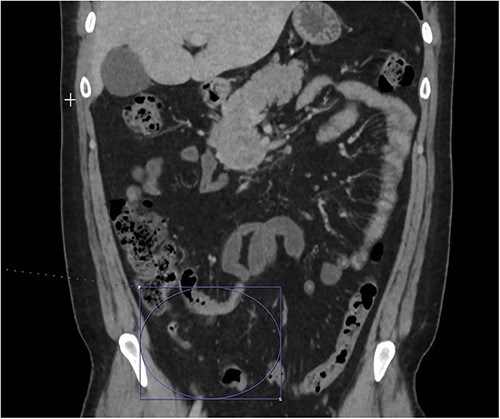

On presentation to the emergency department (ED), he was afebrile and normotensive with blood pressure in the 120s/80s though he had sinus tachycardia (heart rate 120–130 s). His abdomen was soft and diffusely tender with point tenderness at McBurney’s point and negative Rovsing’s sign. He had no signs of frank peritonitis. His complete blood count revealed leukocytosis (WBC 11K/μl), lactic acidosis (lactate 3 mmol/l), and mild transaminitis with AST 72 and ALT 101. An intravenous (IV) contrast-enhanced computed tomography scan of the abdomen/pelvis demonstrated a mildly dilated appendix (~8 mm) with surrounding fat stranding but no appendicolith, perforation, or abscess (Fig. 1). Interestingly, a partial portal vein (PV) and superior mesenteric vein (SMV) thrombosis were also noted (Fig. 2). Initial blood cultures were collected, which remained without growth.

A hyperemic and inflamed appendix can be seen without an abscess, perforation, or appendicolith.